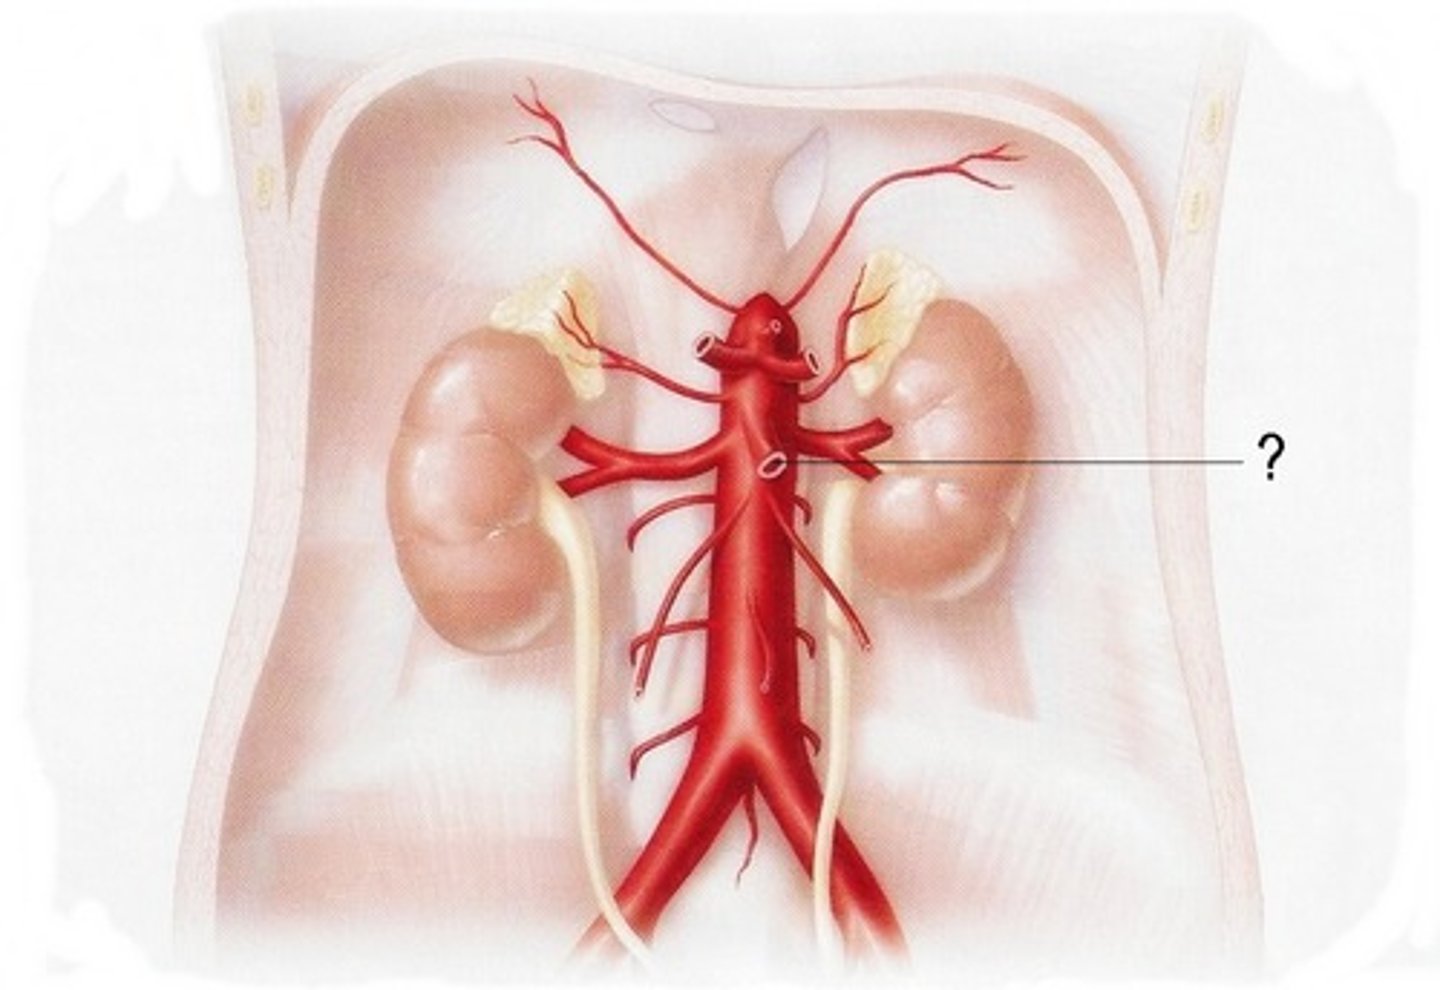

renal artery

serves the kidneys

gonadal artery

serves reproductive organs